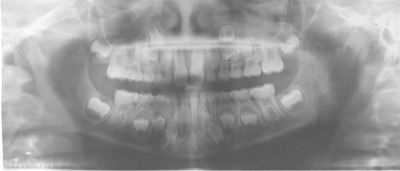

One case posted to the community involved a 13-year-old with a lingually displaced UL3 and plans for full braces, extraction of the primary ULc, and possible exposure and ligation (Figs. 1–5). The treating orthodontist asked: How likely is this canine to correct on its own after extraction?

Fig. 2